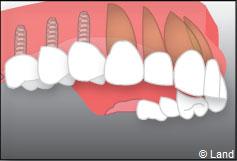

Exemple d’un implant unitaire pour remplacer une dent antérieure manquante.

L’implant est placé dans l’os le plus souvent par vissage et doit avoir une liaison forte avec l’os. Le praticien replace alors la gencive et pose des points de suture.

Pour finir, une prothèse sera mise sur cet implant qui se comportera comme une racine artificielle.